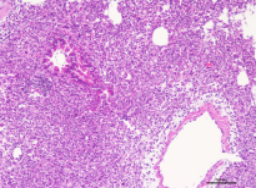

2.1HE检测